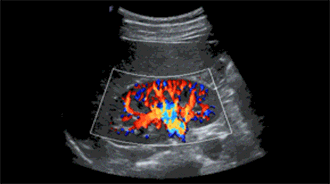

微血流成像

传统